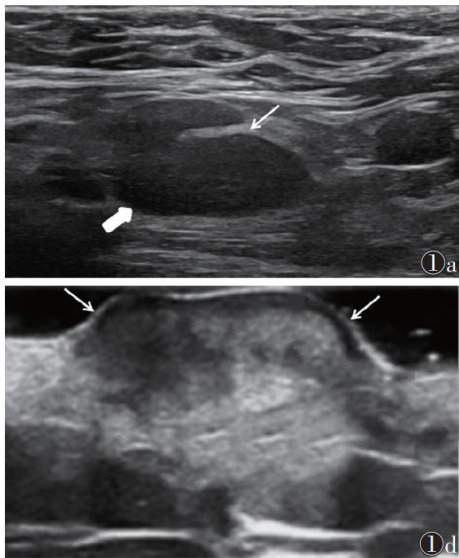

[摘要]目的:应用E-cervix宫颈弹性成像技术探讨正常妊娠孕妇不同孕期宫颈弹性参数的变化规律。方法:选取常规产检孕妇185例行E-cervix宫颈弹性成像,随访排除早产8例、胎儿严重畸形3例,最终纳入174例,其中妊娠12周49例妊娠,16周24例,20周24例,24周21例,28周21例,32周18例,36周17例。记录174例的弹性对比度指数(ECI)硬度比(HR)宫颈内口应变平均值(IOS)、宫颈外口应变平均值(EOS)、宫颈内外口应变比值(IOS/EOS)等宫颈弹性参数,分析宫颈弹性参数与孕周的关系并建立回归方程。结果:随孕周增加,HR呈降低趋势,ECI、IOS、EOS、IOS/EOS均呈升高趋势(均 P<0.05 )。HR与孕周呈负相关( r=-0.175 P=0.021 ),其线性回归方程为: HR=77.409-0.234× 孕周;ECI、IOS、EOS均与孕周呈正相关 (r=0.433,0.452 0.291;均 P=0.001 ),其线性回归方程分别为:

孕周, IOS=0.160+0.004× 孕周, EOS=0.204+0.003× 孕周。结论:随妊娠进展,正常妊娠孕妇宫颈的不均质性不断增加,宫颈硬度不断降低,且以宫颈内口的硬度降低为著。